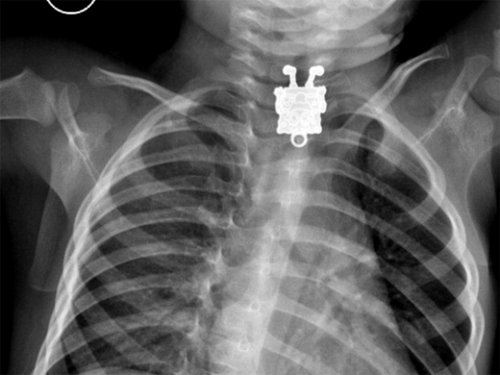

27/01/2015 - Médicos da Arábia Saudita tomaram um susto ao examinar um exame de raio-X de um garoto de 1 ano e 4 meses que tinha se engasgado com alguma coisa. O que eles não sabiam era que o objeto era um pingente do Bob Esponja que podia ser visto com detalhes no esôfago do paciente.

A médica afirmou que o primeiro raio-X, tirado com o garoto deitado de lado, mostrava um pequeno objeto, que os médicos pensaram ser um grampo, mas, ao receberem o resultado do exame feito de frente, viram que era mesmo um pingente do personagem.

""Bob Esponja", eu gritei! Fiquei impressionada com os detalhes visíveis! Você podia ver as sardas, os sapatos e os dedos!", escreveu ela em um email ao 'LiveScience'.